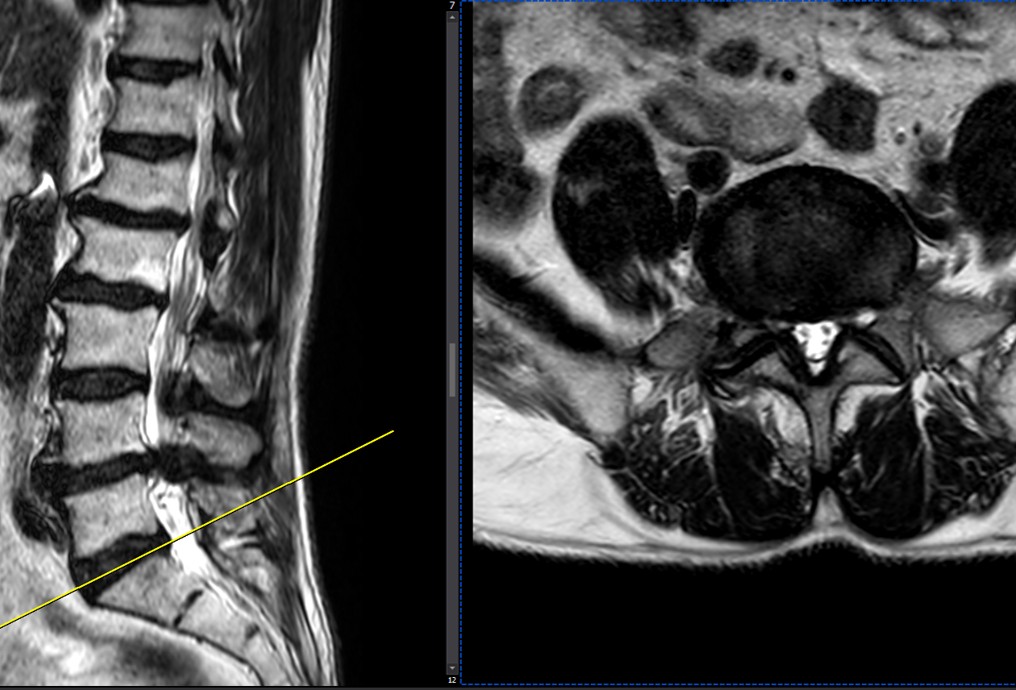

41 years old man presented to my clinic in October 2023 with acute and sever R neck pain with radicular pain to his R upper extremity along C6 dematom since 2 weeks ago. Examination didn’t show any upper motor signs. Was suggested urgent surgery

I ordered EMG/ NCV : showed mild R C6, C7 irritation without any active axonal loss

In his MRI was reported R. para R. IVF Massive extrusion. I decided to control his pain and manage this patient with reevaluation of patient every other session. For 5 sessions i just used acupuncture and laser and IFC and mild adjustments to his R. T3-T7 and mild arthosteem to above and below involved segment. Cervical adjustment considered contraindicated for this patient. From session 6th- 8th i started to use mild/gentle cervical decompression. He used soft cervical collar all the time. His pain decreased by 80 percent

I gave him cervical traction pump to be used 3-5 times per day at home for the next 3 months and i released the patient. He was evaluated every week once for one month and after that every 2 weeks. After 3 month I repeated MRI. Size of the herniated disc was reduced greater than 50 percent. Asked him to do another mri in 6 months

In general: Precise selection of the patients, examination,diagnosis, plan of management, reevaluation and treatment can be done by doctors of chiropractic for the patients with spinal disc herniation and stenosis Moreover giving reasonable time to these kind of patients under direct supervision by their chiropractic doctors can prevent unnecessary surgery. Proper selection of these kind of patients is another important fact that can be done precisely by chiropractors.

MRIs before and after proper management of this patient: